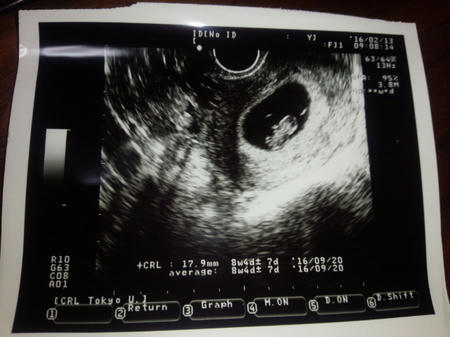

そんな会話の後に超音波検査。

お、お、お、お、お、おおきくなってる

明らかに大きくなってる

ってかなんか動いてる

「これ、動いてます?」

「心臓ですね」

脈拍が確認できるとは聞いていてけれども、こんなに派手に確認できるとは思ってなかった。

胸のあたりでトクトク動いてるのが拍手でもしてるみたいに見えた。

予定日も確定。当初の見立て通り9月20日頃。

わし「今、どのくらいの大きさですか」

先生「ええと、17~18mmくらいですね」

わし「じゅうなな・・・(手を広げる)」

先生「いやミリだから」

主人「2㎝未満だから」

まだ親指くらいかー